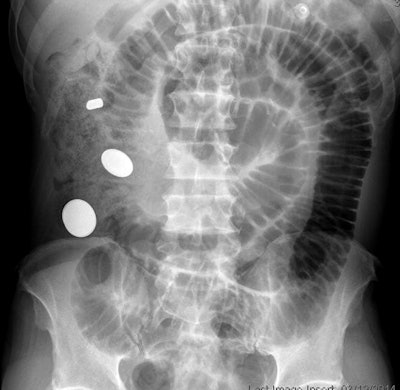

Coins are the most commonly ingested type of foreign body and account for up to 70% of the cases in children, they wrote. But make sure it's a coin and not a button battery, Tseng told AuntMinnie.com. The battery will have a "halo" sign at high magnification on x-ray.

In situations where a patient has aspirated a life-threatening object, bronchoscopy and laryngoscopy are standard diagnosis methods. But for nonlife-threatening items, two-view chest and neck x-rays can be used for the initial evaluation, the authors wrote. When it comes to detecting illegal drugs ingested by condom, balloon, or plastic, x-ray's performance can be variable, with false-negative rates as high as 23%; CT with intravenous contrast works better, according to Tseng and colleagues.